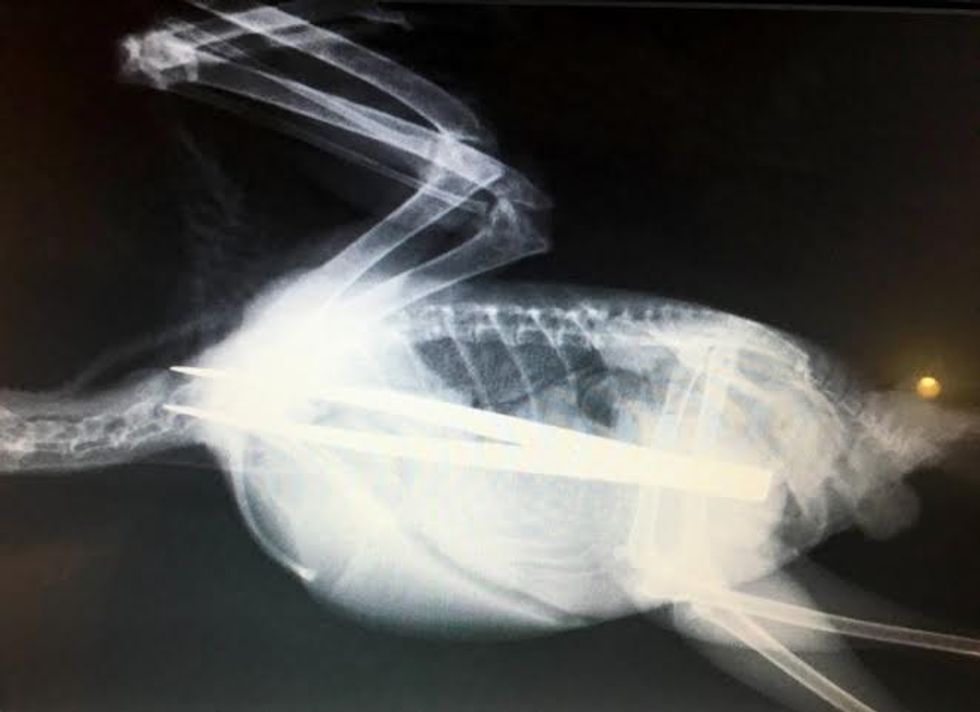

705:"PIC FROM CATERS NEWS - (PICTURED: The Jackdaw) - A young bird that swallowed a pair of TWEEZERS was saved after quick-thinking vets plucked them from him stomach. The greedy jackdaw wolfed down the metal tongs which x-rays revealed had stretched the full length of his body. Vets were concerned that the internal damage caused to the young bird would be too great but following a delicate hour-long procedure the jackdaw from Swadlincote, Derbyshire, is now on the mend. Wildlife vet Dr Bev Panto from RSPCA Stapeley Grange Wildlife Centre said: When I saw the x-rays and the size of the tweezers he had swallowed, I thought there was absolutely no chance this poor jackdaw could survive. SEE CATERS COPY.

Një zog i vogël që ngjan më së shumti me sorrën, ia ka dalë të përpijë një palë pinca që janë të gjata sa trupi tij.

Shpendi i njohur si shumë kureshtar, është zbuluar se ka një palë kapëse metalike, pasi veterinerët e kanë fotografuar me anë të rrezeve X, transmeton Telegrafi.

Mjekët nuk kanë dhënë shanse shpëtimi, meqë operimi ka qenë shumë i gjatë dhe i mundimshëm.

Por, zogu i vogël ia ka dalë të shërohet dhe t’i kthehet gjendjes normale. /Telegrafi/